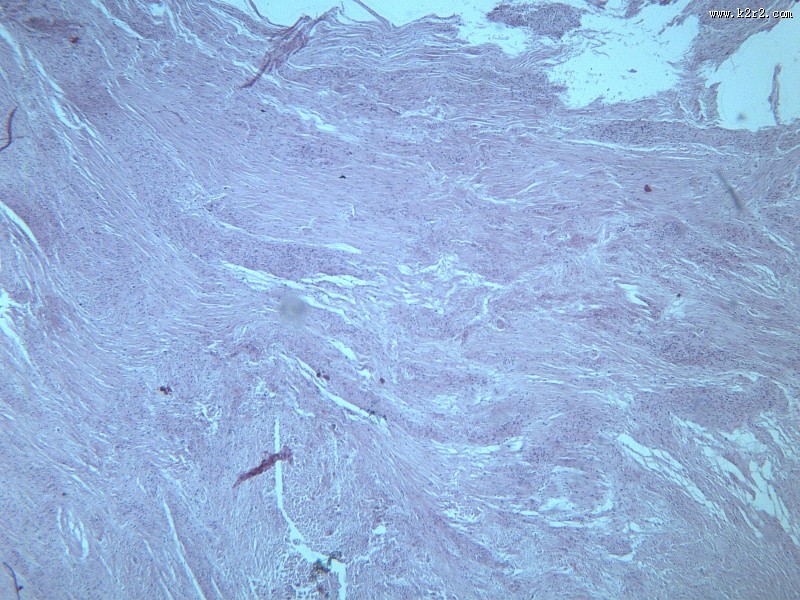

纤维瘤大全 - 第3张

纤维瘤大全

图集中 / 共有 12 张图片

乳腺纤维腺瘤

纤维肉瘤大全

医学

显微切片

肿瘤

fibroma

纤维瘤